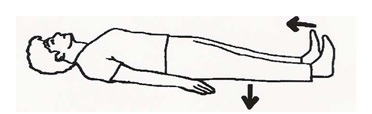

به پشت دراز بکشید و پاها را صاف کنید، مچ پاها را رو به بالا خم کنید و زانوها را محکم به پایین روی تخت فشار دهید. 5 ثانیه در این حالت بمانید، سپس 5 ثانیه استراحت کنید. این حرکت را 10 بار تکرار کنید.

حوله لوله شدهای را زیر پاشنه بگذارید. زانو را ضمن فشار دادن پشت زانو به تخت کاملاً صاف کنید. 3 تا 5 ثانیه در این حالت بمانید، سپس استراحت کنید. این حرکت را 10 بار تکرار کنید.